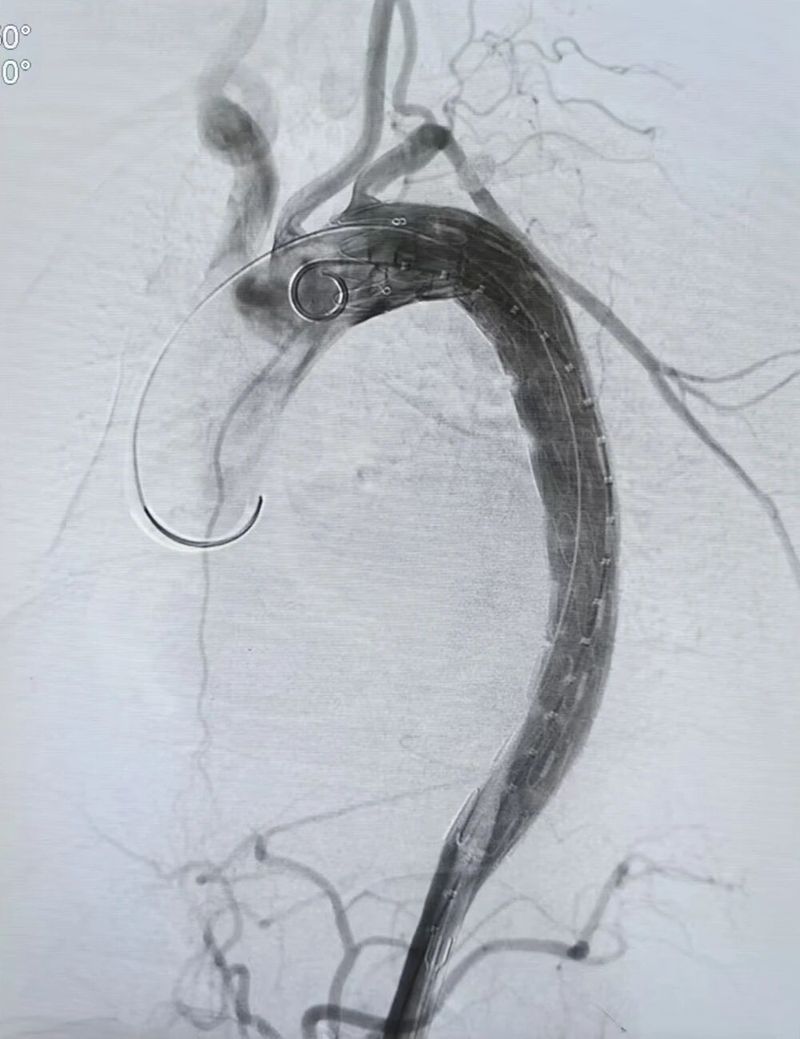

在手术中,心脏血管外科团队为5例A型夹层患者成功实施“孙氏手术”等顶级复杂术式,在深低温停循环条件下完成升主动脉及主动脉弓的精准替换与重建;对3例B型夹层患者则采用“主动脉覆膜支架腔内修复术”,通过微创介入成功隔绝夹层破口。这两类手术的成功开展,彰显了我院在主动脉疾病全谱系救治方面的成熟技术。

B型术后复查